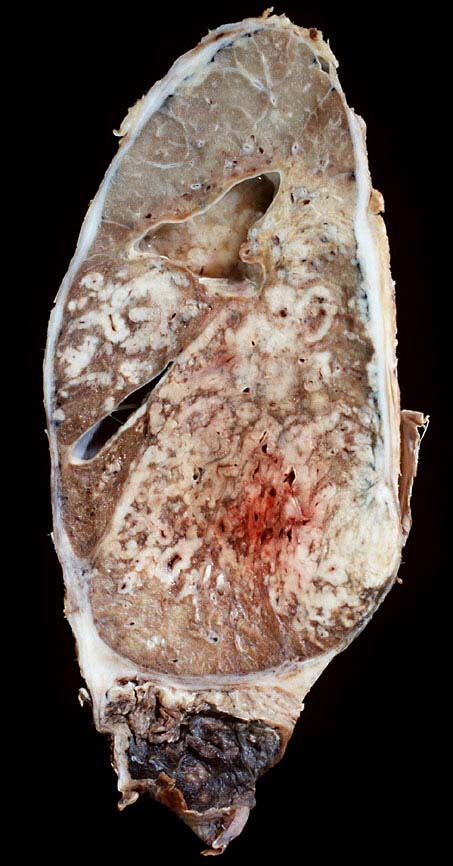

Das metastatische Wachstumsmuster von primären Bronchuskarzinomen und extrapulmonalen Tumoren innerhalb der Lunge ist variabel. Hämatogene Metastasen imponieren makroskopisch als multiple scharf begrenzte rundliche Knoten in allen Lappen meist in peripherer Lage. Der metastatische Befall von Lymphknoten kann durch direkte Tumorinfiltration durch den Primärtumor erfolgen (=per continuitatem) oder über die Lymphgefässe. Bei einer ausgeprägten lymphogenen Tumorausbreitung erscheinen subpleurale mit Tumor gefüllte Lymphgefässe makroskopisch als prominente weisse Streifen. Mikroskopisch lassen sich Tumorinfiltrate in peribronchialen und perivaskulären Lymphgefässen nachweisen (=Lymphangiosis carcinomatosa). Hepatozelluläre Karzinome metastasieren typischerweise in Form von Tumorembolien (> 1279) hämatogen in die Lunge.

• Sternförmiges Karzinom mit zentraler Vernarbung mit reichlich schwarzem Anthrakosepigment.

• Das Karzinom ist aufgebaut aus tubulären und kribriformen Drüsen.

• In den sternförmigen Ausläufern finden sich erweiterte Endothelausgekleidete Lymphgefässe in der Nachbarschaft von Blutgefässen.

• Die erweiterten Lymphgefässe enthalten solide Tumorzellaggregate.